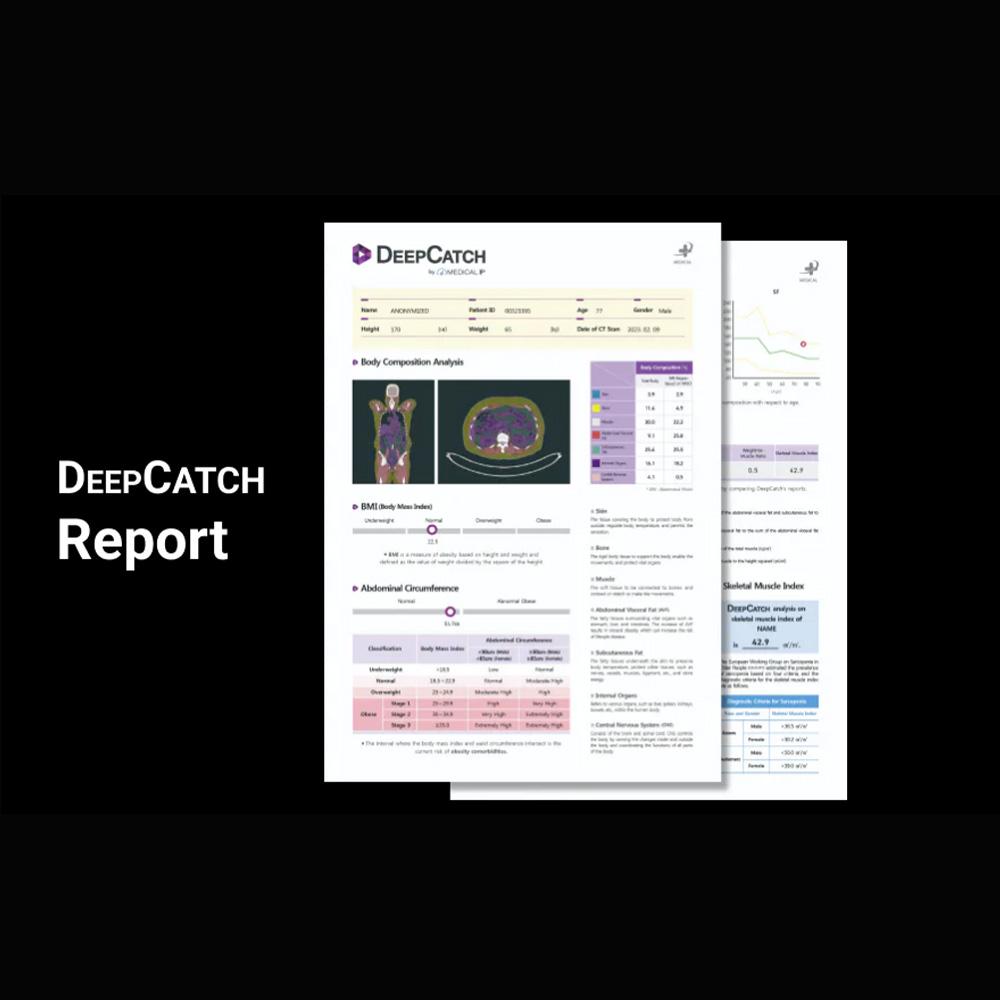

Prevention by Early Detection of Metabolic Diseases

Biomarkers for sarcopenia, obesity, Adipopenia

Provides automatic analysis report on body composition analysis results

Prevention by Early Detection of Metabolic Diseases

Biomarkers for sarcopenia, obesity, Adipopenia

Provides automatic analysis report on body composition analysis results

MFDS Class 2, FDA Approval